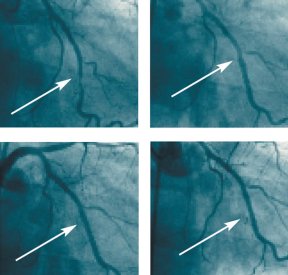

Doctors attack atherosclerosis to prevent it from triggering heart disease, one of the leading causes of death in the United States. Which treatment they choose depends on the severity of the artery clogging, often detected with angiograms, which are x-ray images of blood vessels. People with mild atherosclerosis may receive only medications designed to prevent blood clots and cholesterol-lowering drugs to block any further fatty buildup inside arteries. In people who have severe blockages in vessels serving the heart, cardiologists typically perform surgery to bypass the diseased arteries.

In early September at the European Society of Cardiology Annual Congress in Stockholm, an international team of researchers reported tests of a stent coated with a polymer that releases sirolimus, an immune-suppressing drug that slows cell growth. The sirolimus coating boosted angioplasty success rates. After about 7 months, only 4 of the 120 patients who received a drug-coated stent had died, suffered a heart attack, developed blood clots, or needed a follow-up heart procedure. After the same amount of time, 32 of the 118 people with a bare-metal stent had experienced one of those adverse events. Researchers didn’t spot restenosis in angiograms of any patient implanted with the drug-coated stent, which is made by Cordis, a Johnson and Johnson company in Miami Lakes, Fla.